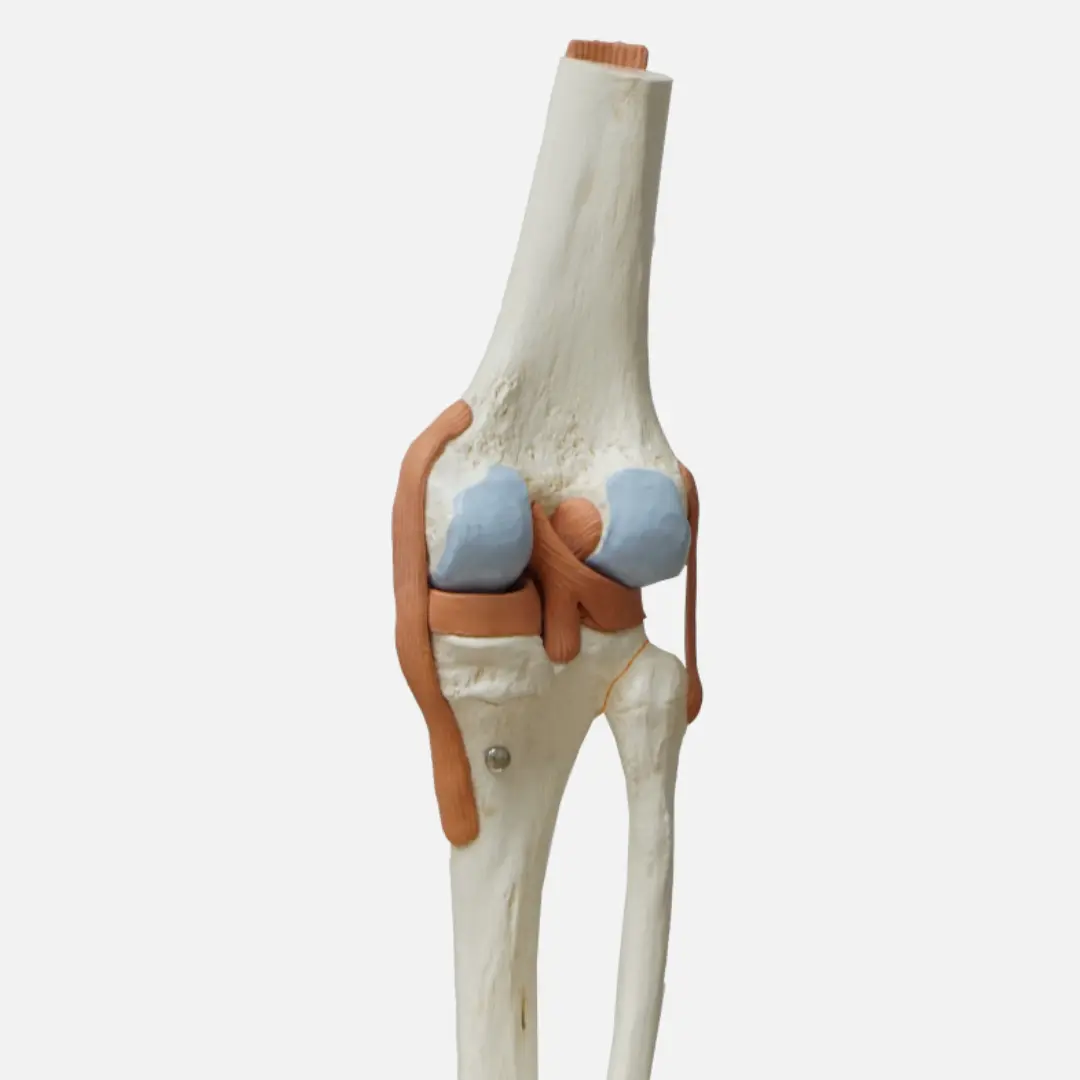

무릎 연골 손상 후에는 꾸준한 관리가 중요합니다. 일상생활에서의 습관 개선과 적절한 운동은 증상 악화를 방지하고 재활을 돕는 데 큰 역할을 합니다. 우선 무릎에 과도한 부담을 주는 활동은 피하는 것이 좋습니다. 장시간 서 있거나 무거운 물건을 드는 행동은 자제해야 합니다.

규칙적인 운동은 무릎 주변 근육을 강화하여 관절을 안정화시키는 데 도움이 됩니다. 다만, 무리한 운동보다는 수영, 자전거 타기, 가벼운 걷기 등 무릎에 부담이 적은 운동을 선택하는 것이 좋습니다. 체중 관리 또한 매우 중요합니다. 과체중은 무릎에 가해지는 하중을 증가시켜 연골 손상을 악화시킬 수 있으므로, 건강한 식단과 규칙적인 운동을 통해 적정 체중을 유지해야 합니다. 이 외에도 무릎 보호대 착용, 바른 자세 유지, 틈틈이 스트레칭을 해주는 것도 좋은 관리 방법입니다.